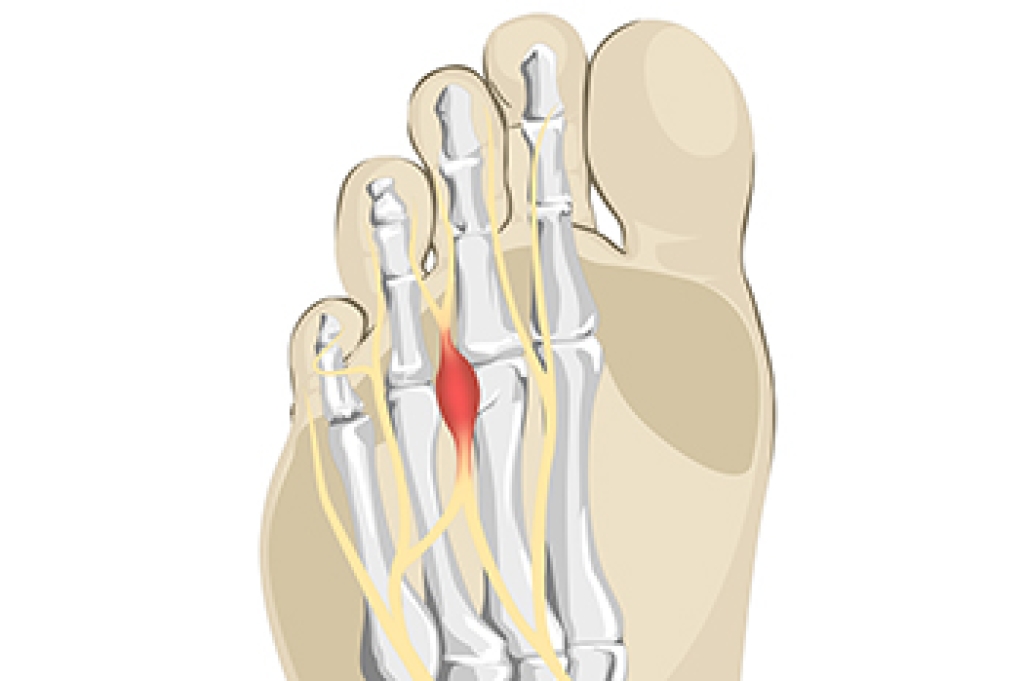

- Plantar fasciitis is another foot condition that can be caused by obesity. Plantar fasciitis is an inflammation of the tissue along the bottom of the foot, which causes pain and stiffness while walking and climbing stairs.